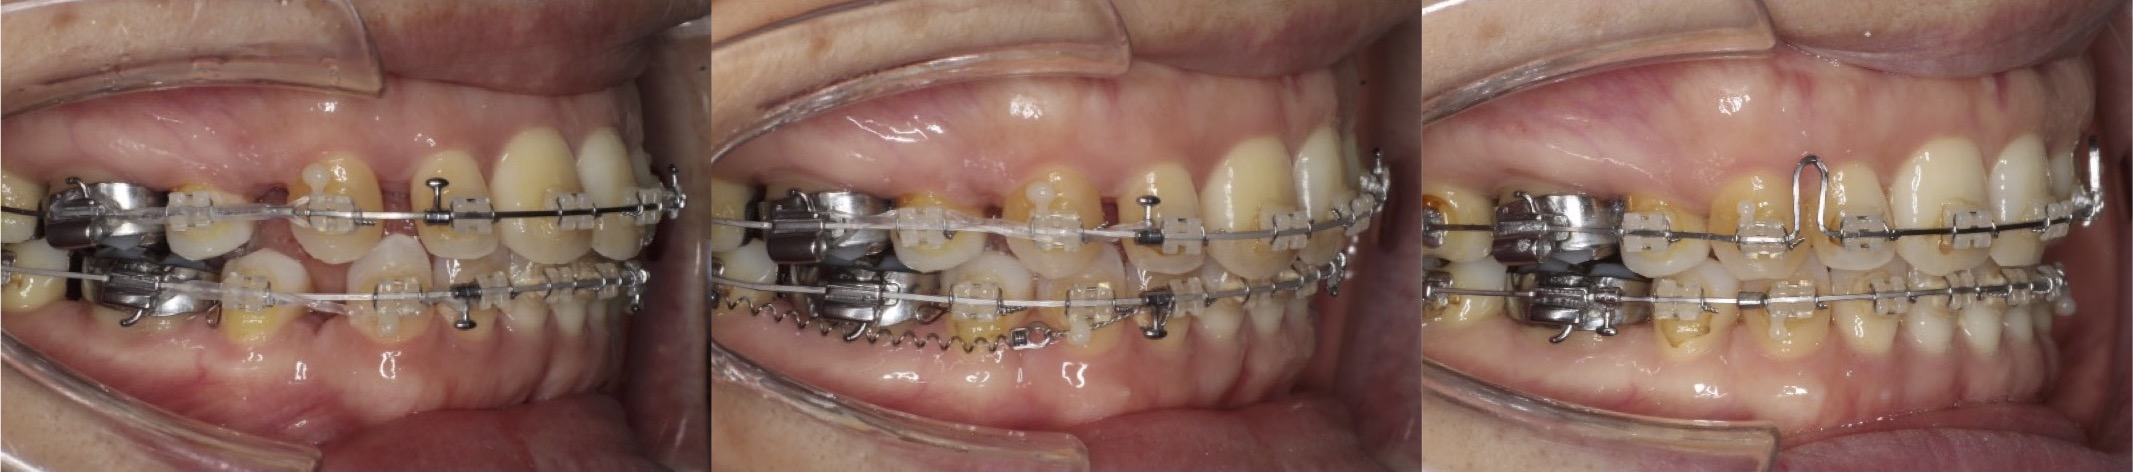

43歳女性・唇側矯正装置・抜歯

<症例概要>

主訴:前歯のがたつきと・かみ合わせ

年齢・性別:43歳女性

住まい:千葉県佐倉い市

症状:叢生・前歯交叉咬合・左上5番萌出不全

治療方針:右上下4番・左上下5番(計4本)

治療装置:唇側矯正装置

固定装置:リンガルアーチ

治療期間:2年6か月

リテーナー:下フィックス+上下クリアタイプ

治療費用:968,000(税込)

代表的副作用:痛み・治療後の後戻り・歯根吸収・歯髄壊死・歯肉退縮

▶︎その他の副作用

抜歯矯正ではふつう4番を抜歯するのですが、歯の状況によっては5番を抜歯することもあります。左上の5番の歯が半分弱しか出てきてないことと、左下の5番が大きく外側に転位していることから、左側のみ5番を抜歯し矯正治療を行いました。やや歯列の正中線は、4番を抜歯した右側に引っ張られたのですが、患者さんはそこまで気にしていませんでした。